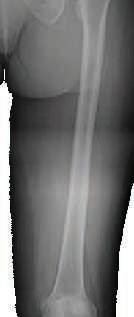

Nancy Antone, 72, is one of our grateful Campbell Clinic trauma patients. She was working in her yard when she fell in late 2022, breaking the top of her right femur. During the next year, she underwent five surgeries—once to implant a metal rod, once to address an E.coli infection, a third operation to replace the incorrectly situated rod with an antibiotic one, a fourth operation to implant an all-new metal rod, then finally a knee replacement. After her original operation at Baptist-Desoto, Ms. Antone consulted with Dr. Marc Mihalko, then was under the care of Drs. Cosgrove and Gregory Dabov.